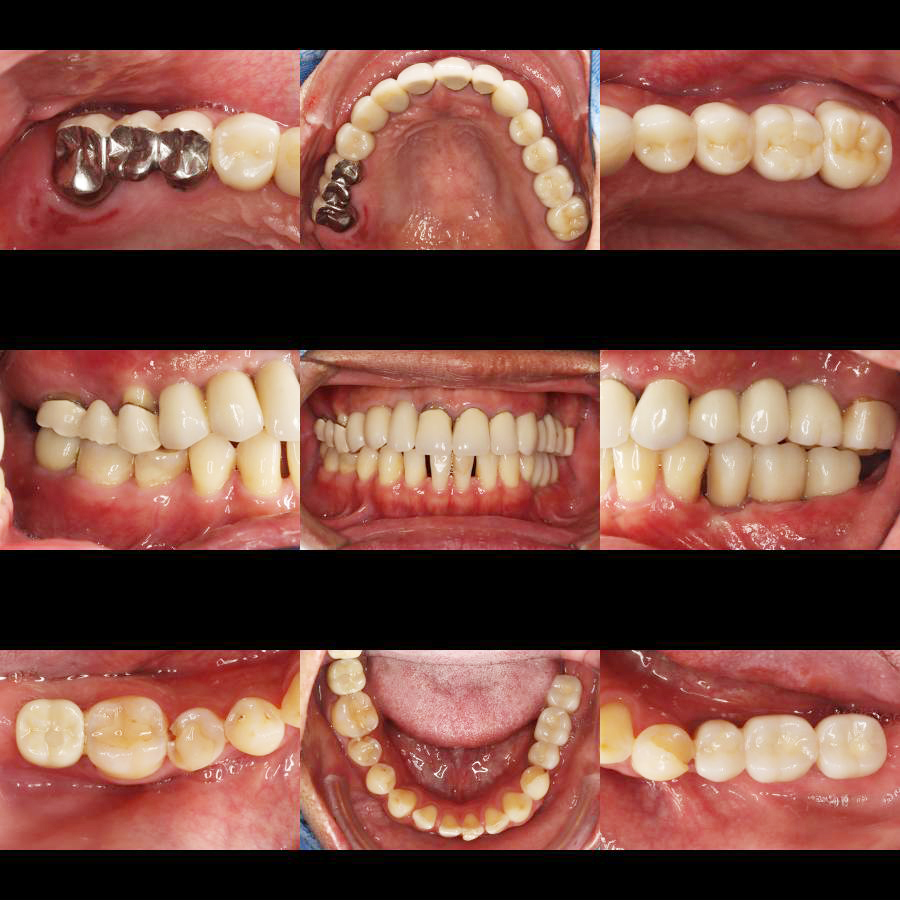

植體牙橋設計: 觀察影像下方,我們利用數顆植體支撐起整片假牙(牙橋設計),這能有效減少手術次數與費用,同時維持極佳的穩定度。

咬合高度的重建 (Vertical Dimension):

多顆缺牙常導致臉部下三分之一塌陷,透過植牙,我們重新找回了患者失去的咬合高度,改善咀嚼功能。

力學分佈的平衡 (Force Distribution):

植體的分佈必須考慮到對咬牙的關係,影像中顯示,上下顎的植體位置精準對位,確保咬合力能垂直傳導至骨組織,避免植體鬆脫。